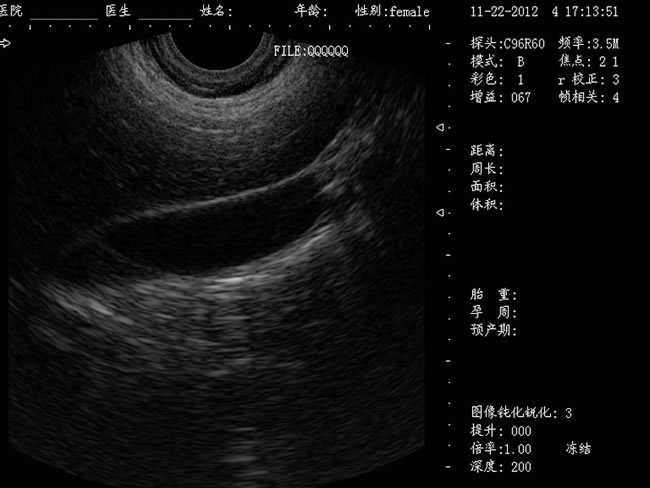

定位精確 手術效率高:實時動態頻率掃描等全數字超聲成像技術、生成精確的圖像引導手術器械迅速到大手術位置,避免損傷子宮內膜和子宮穿孔的現象,即減輕了患者的痛苦又極大提高了手術效率。

選配:CXA60R/3.5MHz 凸陣探頭

隨著醫療技術水平的提高,目前婦產科手術中所應用的相關設備也有了加大的改進。尤其是在人工流產手術中,將B超婦產科手術監視儀應用到手術過程中,彌補傳統手術中所采用設備的不足之處,減輕手術中患者的疼痛感覺,使得手術順利的完成。這種儀器相比于傳統的儀器來說,其在操作上更為方便和簡單,能夠對妊娠反應有很好的療效。